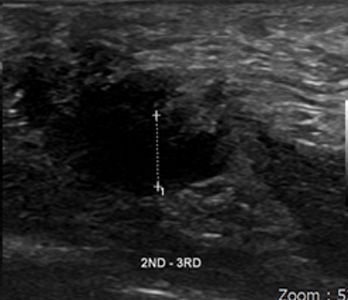

55세

여성 지간신경종

Before

2020.05.09

After

2020.08.06